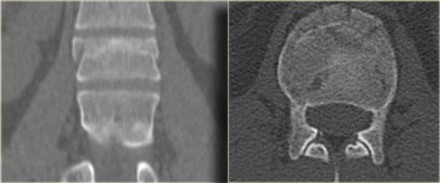

On the left a coronal reconstruction and an axial image at the level of the fracture.

Continue with the MR.